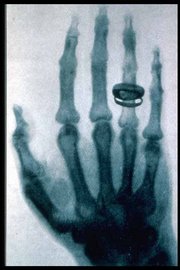

Am 22.12.1895 fertigte Wilhelm Conrad Röntgen diese Aufnahme der rechten Hand von seiner Frau Bertha an. Die Belichtungszeit betrug mehr als 30 Minuten. Dieses Datum gilt auch als „Geburtsstunde“ der Radiologie. Die Besonderheit dieser Aufnahme ist der „frei schwebende“ Ring. (Quelle : https://roentgenmuseum.de )